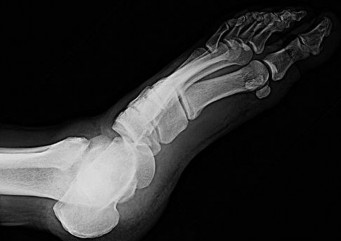

Figure 54 is the lateral radiograph of a 55-year-old man who is evaluated for a 2-year history of pain and stiffness of his right metatarsophalangeal (MTP) joint. Upon examination he has dorsal bossing, severe crepitation, and pain

with passive range of motion. There is pain with the "grind" test. Dorsiflexion is limited to 0 degrees. No sesamoid tenderness is present. What is the most appropriate surgical treatment?